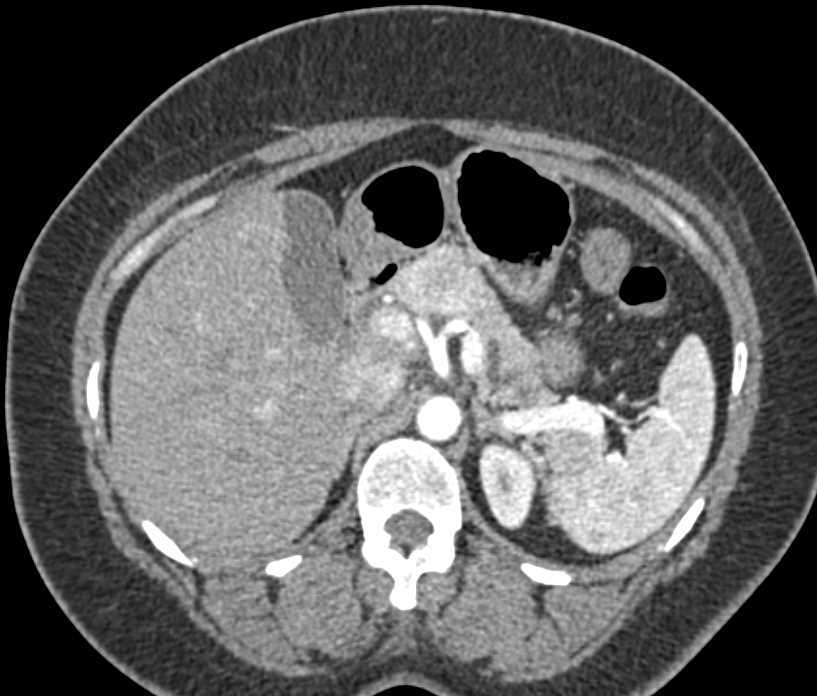

Neuroendocrine Tumor Body of Pancreas